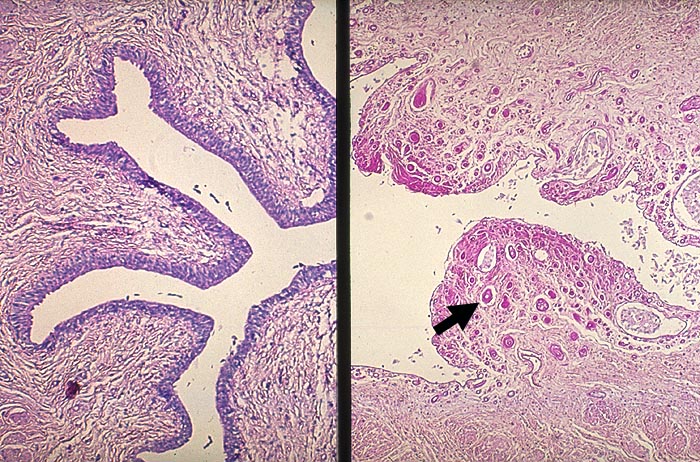

Kapillarosklerose bei Phenacetinabusus

Im Vergleichsureter links sind praktisch keine Kapillaren erkennbar. Bei Analgetika-Abusus treten die Kapillaren als stark PAS-positive Strukturen deutlich hervor. Das umliegende Bindegewebe ist leicht sklerosiert und ebenfalls stärker PAS-positiv als im Vergleichsureter.